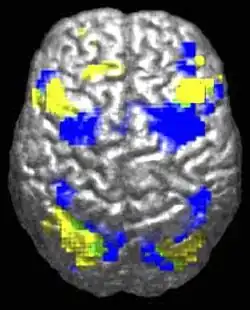

При анализе работы мозга лиц с расстройствами аутистического спектра паттерны сниженной и аберрантной активации различаются в зависимости от того, какую задачу выполняет испытуемый — социальную или не-социальную.[87] Существуют свидетельства того, что при аутизме нарушена функциональная связность сети пассивного режима работы мозга (англ. default network), обширной системы взаимодействующих участков головного мозга, активной в состоянии, когда человек не занят выполнением какой-либо задачи, связанной с внешним миром, а, напротив, бездействует, отдыхает, грезит наяву или погружён в себя. В то же время сохранена связность сети оперативного решения задач (англ. task-positive network), играющей роль в поддержании внимания и целенаправленном мышлении. Отсутствие негативной корреляции в активации двух сетей у аутистов предполагает наличие дисбаланса в переключении между ними, что может свидетельствовать о нарушениях самореферентного мышления.[88] При нейровизуальном исследовании работы поясной коры, проведенном в 2008 году, у лиц с расстройствами аутистического спектра был обнаружен специфический паттерн активации этой части мозга.[89]

Согласно теории недостатка связности, при аутизме может быть снижена функциональность высокоуровневых нейрональных связей и синхронизации при избытке низкоуровневых процессов.[92] В пользу теории говорят данные фМРТ-исследований[31] и результаты одного исследования волновой активности, позволяющего предположить избыток локальных связей в коре и ослабленную функциональную связность лобной доли с другими областями коры.[93] В других работах предполагается, что недостаток связности преобладает внутри полушарий и аутизм представляет собой расстройство ассоциативной коры.[94]